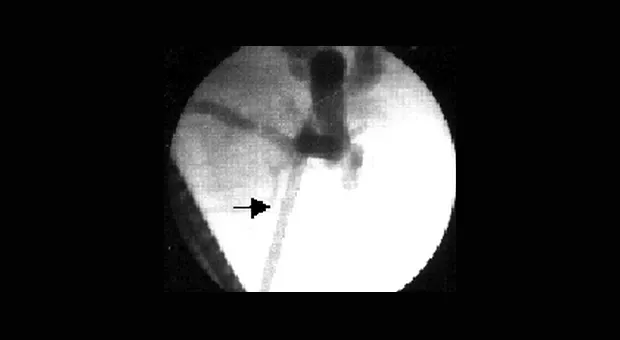

Наш опыт в эндоскопическом стентировании при холангиокарциноме менее оптимистичен, наиболее часто приходится сталкиваться с запущенными формами заболевания (например, тотальном поражении под печеночных желчевыводящих путей), когда необходимо установка стента в правый или левый печеночный проток, что не всегда технически возможно. Пример успешного стентирования показан на рис. 6.